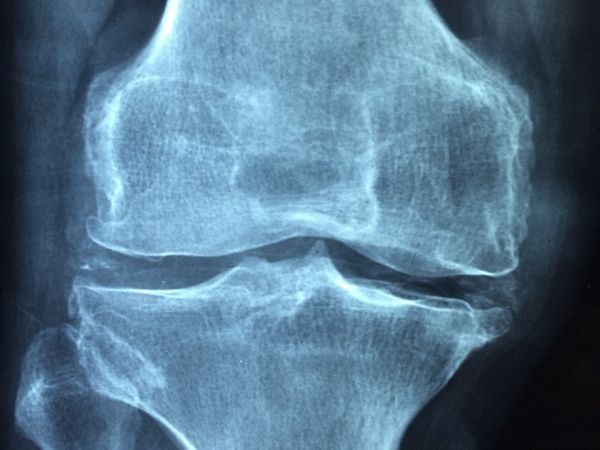

Известен факт е, че остеопорозата и диабетът са широко разпространени състояния със значима свързана заболеваемост и смъртност. Пациентите със захарен диабет имат повишен риск от костни фрактури. При болните с диабет тип 1 рискът се повишава приблизително 6 пъти, а при пациентите с диабет тип 2 опасността е 2 пъти по-голяма в сравнение с хората без захарен диабет.

Високата кръвна захар има неблагоприятен ефект върху костите, ето защо пациентите с диабет трябва редовно да изследват своята костна плътност. Повишените нива на инсулин водят до ускорен костен обмен и костна загуба, което от своя страна може да доведе до остеопороза. Хипергликемията (повишените нива на кръвна захар) увеличава оксидативния стрес, което води до възпалителни процеси в цялото тяло и в частност на костите.

Данните показват, че след 50-годишна възраст една от всеки три жени и един от всеки пет мъже ще получи най-малко една фрактура вследствие на чупливост на костите. Рискът от бедрена фрактура през живота на жената е по-голям от опасността от развитие на рак на гърдата, на ендометриума и на яйчниците взети заедно.

Счупването на бедрената шийка води до повишение с до 20% на смъртността в рамките на 1 година. За съжаление, смъртността в резултат на остеопорозата у нас е по-висока (184 на 100 000), отколкото в Европейския съюз (116 на 100 000).